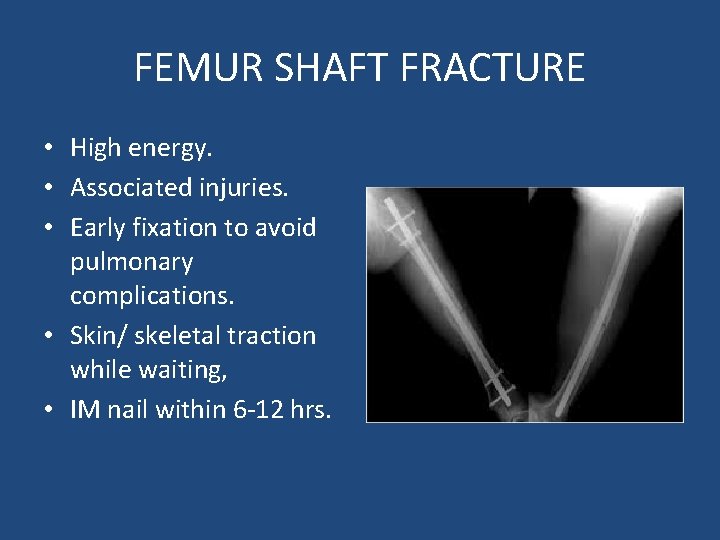

FEMUR SHAFT FRACTURE • High energy. • Associated injuries. • Early fixation to avoid pulmonary complications. • Skin/ skeletal traction while waiting, • IM nail within 6 -12 hrs.